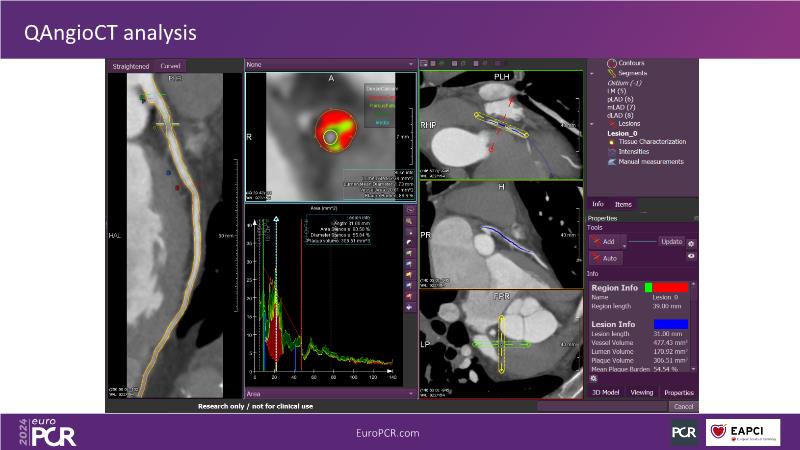

QFR: the next-generation diagnostic tool for epicardial and microvascular disease in the cathlab

Join this session to delve into the cutting-edge capabilities of the newest QFR technology, allowing for rapid coronary vessel analysis in under 30 seconds. Gain insight into the diagnostic potential of QFR-IMR for assessing coronary microvascular dysfunction and understand its implications for patient care. Explore the transformative impact of QFR on treatment planning, paving the way for innovative approaches to managing coronary artery disease.

- To learn how the newest QFR technology enables coronary vessel analysis in under 30 seconds

- To learn how QFR paves the way for new horizons in treatment planning